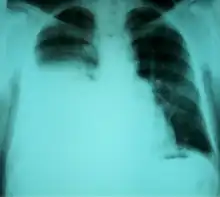

| Chest X-ray showing a hepatic hydrothorax in a person with cirrhosis | |

Hepatic hydrothorax is a rare form of pleural effusion that occurs in people with liver cirrhosis. It is defined as an effusion of over 500 mL in people with liver cirrhosis that is not caused by heart, lung, or pleural disease. It is found in 5–10% of people with liver cirrhosis and 2–3% of people with pleural effusions. It is much more common on the right side, with 85% of cases occurring on the right, 13% on the left, and 2% on both.[1] Although it is most common in people with severe ascites, it can also occur in people with mild or no ascites. Symptoms are not specific and mostly involve the respiratory system.